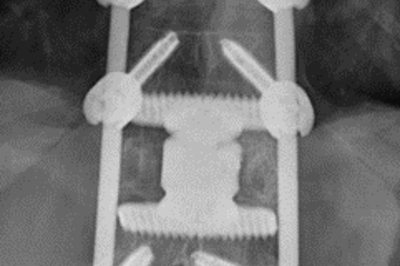

• Verschraubter Wirbelbruch

Röntgenbild verschraubter Wirbelbruch